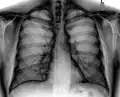

Рентгенограмма грудной клетки в прямой проекции, норма.

При изучении рентгеноанатомии органов грудной клетки обращают внимание на рентгеновскую структуру видимых костей и мягких тканей грудной клетки; форму и прозрачность для рентгеновских лучей областей, на которые проецируется лёгочная ткань (так называемых «лёгочных полей»), а также их структуру, сформированную тенями сосудов лёгких («лёгочный рисунок»); расположение и структурность корней лёгких; положение, форму куполов диафрагмы и синусов плевральных полостей; форму и размеры тени средостения (в том числе сердца).

Дополнительные или отсутствующие теневые элементы (затемнения и просветления, снижение или повышение прозрачности лёгочного фона, обогащение или обеднение лёгочного рисунка и т. д.) в теневой картине лёгочной ткани свидетельствуют о патологии. Каждый из дополнительных теневых элементов обладает определёнными характеристиками (положение, число, форма, размеры, интенсивность, структура, контуры, смещаемость), не только имеющими клиническое значение, но и способствующими дифференциальной диагностике, а также имеющими практическую ценность при планировании бронхоскопии, биопсии, оперативного вмешательства и т. д.

В числе патологических рентгенологических находок выделяют очаги или фокусы (ограниченные участки затемнения лёгочной ткани), воздушные полости (участки просветления на фоне лёгочной ткани), плевральный выпот (затемнение плевральных синусов и междолевых щелей или пристеночное затемнение различной распространённости), воздух в плевральной полости (прослеживается тонкая линия висцеральной плевры, отделённая от грудной клетки участком просветления, лишённым лёгочного рисунка), различные типы диффузных изменений (ретикулярный, милиарный, кистозный, по типу «матового стекла», зоны диффузной консолидации).